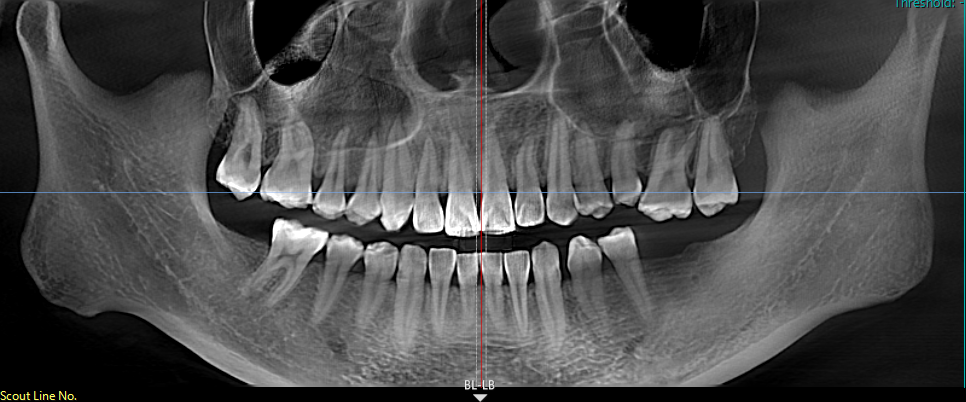

面对此情况,易建飞团队决定采用"正畸-种植联合疗法",先正畸后种植,先改善牙齿排列和咬合关系,为种植牙提供更理想的条件,也为种植牙齿提升美观性、功能性和长期稳定性。这种综合治疗方式能够更好地满足患者的需求,实现更自然、协调的口腔修复效果。

为让患者理解治疗方案,医生耐心解释:"就像盖楼前要先打地基,你的牙齿也需要先“修轨道”,把伸长的牙齿压回去,才能为种牙创造足够的空间。"经过半年的治疗,小王的牙齿不仅重新对齐,种牙后的咬合功能也完全恢复。"现在啃苹果时,两侧牙齿均匀用力的感觉真的太棒了!"她兴奋地说,"以前因为缺牙,我总是不敢大笑,现在终于可以自信地露出笑容了。"

易建飞提醒,后牙缺失超过3个月就需要及时干预,否则可能导致邻牙移位、咬合紊乱等问题。60%的种植失败案例都源于咬合空间不足,而"先正畸后种植"的联合疗法可以有效避免这些问题,甚至减少30%的骨增量需求。